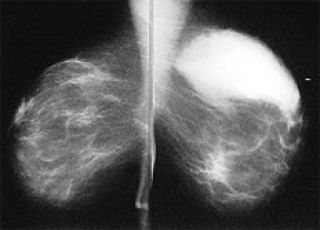

¡Diosa! ¿Por qué no seré más grande de ahí abajo?, me pregunto en plena colposcopia y consiguiente Papanicolaou. Es un instante, un instante nada más, intento convencerme pero todo lo que tengo en la cabeza son lugares comunes sobre la salud de las mujeres y las delicias a las que estamos expuestas. Hay que dejarse escarbar una vez al año para prevenir el cáncer de útero. Hay que sufrir el aplastamiento consensuado de las tetas entre dos planchas de metal para evitar males mayores como no advertir un cáncer de mama. Hay que luchar contra la divulgación irresponsable que cada tanto advierte que tal vez no sería tan bueno someterse a mamografías anuales por el riesgo de la radiación. Una intenta levantar sus banderitas: este año no me hago mamografía, que la ginecóloga se conforme con la ecografía que es menos cruenta. La doctora tiene paciencia y se aviene a negociar conmigo: “Hacemos el examen manual y, si está todo bien, tranzamos”. La responsabilidad de la profesional convierte mi tortura anual en un asunto personal. Tal vez debería agradecérselo. Y sin embargo lo único que me sale es una puteada cuando descubre un nódulo y me dice que no hay manera, que deberé pasar otra vez por la compactadora de tetas.

De vuelta en la sala de espera, espanto el miedo al nódulo con una nueva Cosmopolitan. Ahora el compás de tiempo se abre mientras la secretaria pide las autorizaciones para los exámenes ya realizados y otros trámites administrativos que poco me importan. Encuentro, como podía ser de otra manera, un bonito capítulo sobre tetas en mi moderna revista para mujeres; perdón, para chicas. Habla de todo lo que es necesario saber para tener un escote “hot” –caliente, sí, pero ¡les gusta tanto escribir hot!–, desde cirugías hasta cremas, corpiños y remeras blancas y transparentes que van a “volver loco a tu hombre”. De tanto pensar en tetas me acuerdo de una polémica reciente sobre la edad del destete: las opiniones van desde los nueve meses hasta los ¡siete años! (del niño/a, claro). Todo sea por ellos. Por ellos, cualquier ellos, incluso por ellas. Nunca por una. Estas tetas son mías, pienso, pero una voz insidiosa parecida a la conciencia me dice que si son mías mejor que las cuide y las radiografíe. Ok, para qué discutir, pero ya que son tan nuestras podrían empezar a idear un sex toy para ellas, siempre tan magreadas, aplastadas, revisadas, sujetadas, miradas, sopesadas. Voy a escribir una carta a Cosmo. Necesito saber cómo hicieron para abducir mi cerebro con sólo una hora de espera en un consultorio.